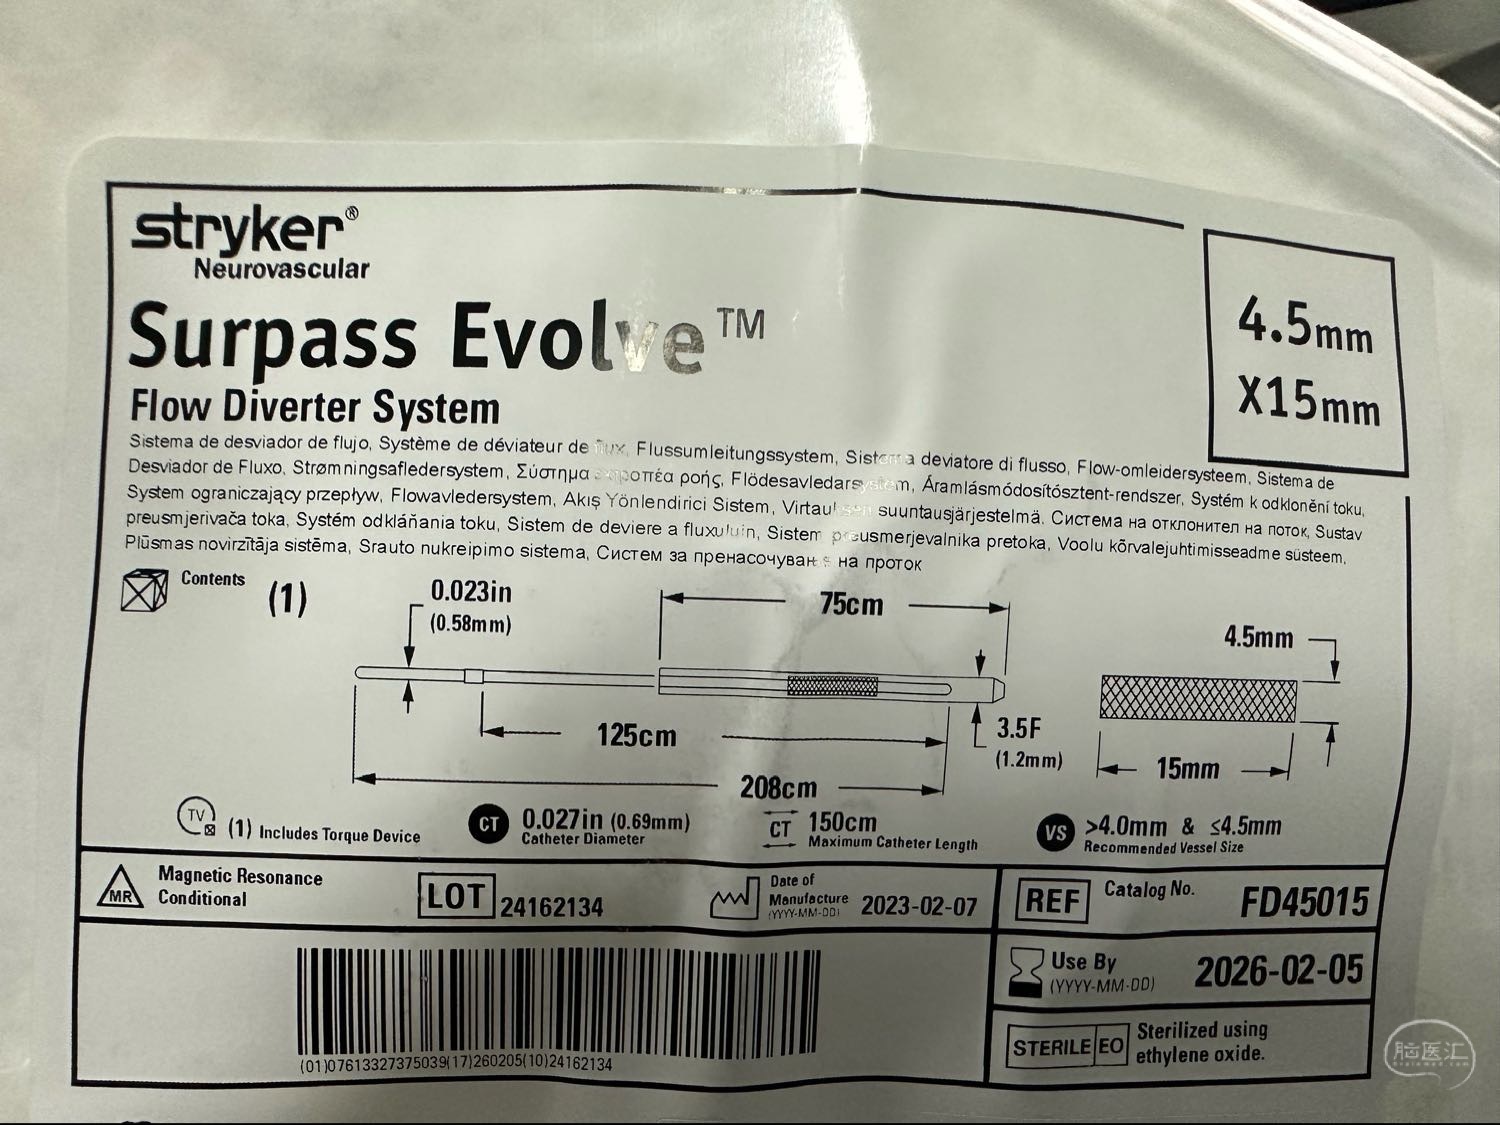

选择的支架得型号4.5*15的支架

选择的支架得型号4.5*15的支架